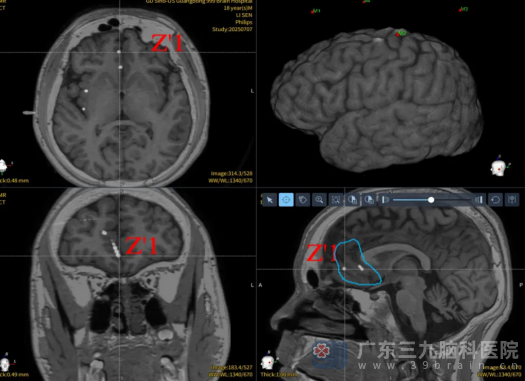

图6:SEEG方案

面对如此复杂的病情,我院神经内三科(癫痫内科)主任李花、费凌霞主任医师及神经外八科二区副主任陈俊喜等迅速组织了病例讨论。经过深入分析,一致认为致痫灶可能位于右侧额叶。虽然核磁共振检查结果为阴性,但发作症状学和脑电图表现不除外颞极、岛叶、颞叶底面新皮层癫痫的可能。为了明确致痫灶及手术切除范围,为患者设计SEEG方案(图6)并置入电极检查。

图7:SEEG检查结果

图8:SEEG检查结果

SEEG检查结果(图7~8),证实了专家们的判断,右侧前扣带回正是患者癫痫发作的源头。在明确了致痫灶后,我院神经外八科二区专家团队为患者制定了个性化的手术方案。